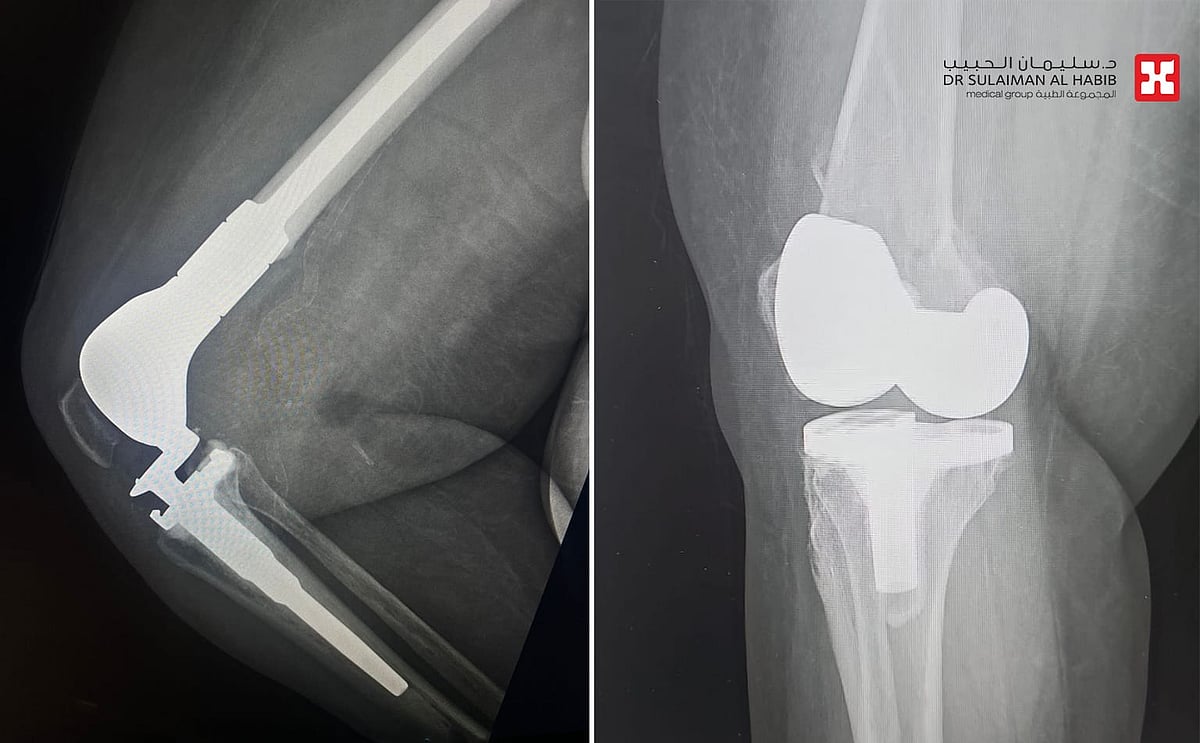

شهد مستشفى الدكتور سليمان الحبيب بالسويدي، إجراء عملية متقدمة لاستبدال الجزء السفلي من عظمة الفخذ Distal Femoral Replacement, DFR لسيدة تبلغ من العمر”80″ عاماً، كانت قد خضعت لعملية استبدال مفصل ركبة قبل عامين، وتعرضت مؤخراً لحادث منزلي عرضي، نتج عنه كسر في أسفل عظمة الفخذ، وعانت من أعراض حادة. ذكر ذلك د. رغيد شبو استشاري جراحة العظام والإصابات واستبدال المفاصل رئيس الفريق الطبي المعالج.